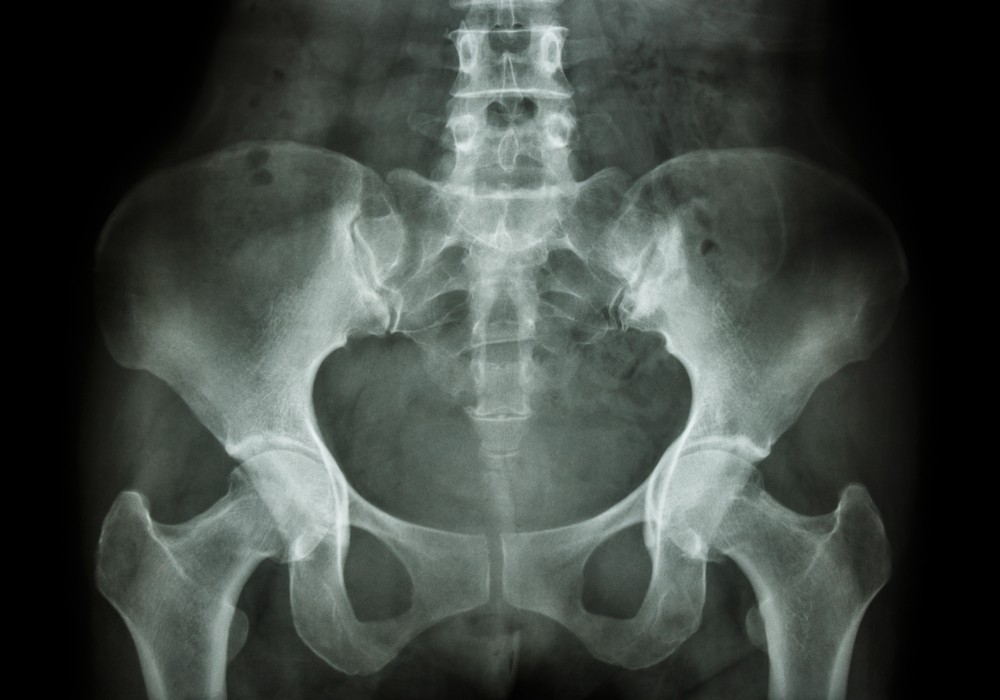

Рентген таза – это неинвазивное исследование анатомического строения и состояния костей на цифровом сканере. Метод исследования основан на избирательном воздействии безопасных доз ионизирующего излучения на разные органы и ткани. Во время процедуры пациент не испытывает дискомфорта или неприятных ощущений. Результатом станет исчерпывающая информация о присутствующих патологиях больших костей и суставов, мышц, сухожилий, а также органов малого таза. Высокая точность рентгеноскопии позволяет визуализировать заболевания на ранних стадиях, что позволит начать своевременное лечение.

Основное назначение рентгена костей таза – это комплексное исследование костей в данной области (тазобедренная, крестец, копчик), связок, мышц и мягких тканей при подозрении на заболевания. Наиболее распространенными состояниями, выявленными при помощи этого метода, являются различные травмы (трещины, переломы, вывихи, подвывихи), патологии костной ткани (артрозы, артриты, остеомиелиты), а также различные аномалии развития.

Расшифровку полученных рентгенограмм производит врач-рентгенолог в течение 2-3 часов после исследования. Пациент получает на руки не только подробный протокол с описанием обнаруженных патологий, но и снимки – распечатки и в цифровом формате. Заболевания проявляются на визуализациях зонами с повышенной эхогенностью, либо же участками с затемнениями и помутнениями. Наибольшее внимание на рентгене таза врач уделяет следующим моментам:

• Верхние и нижние ветви лонных костей не имеют смещений, положение соответствует анатомической норме;

• Состояние головок бедренных костей – наблюдается конгруэнтность в соответствии с вертлужными впадинами, не идентифицируется краевых костных заострений, остеопороза, опухолей;

• Суставные щели имеют размер в соответствии с нормой, что говорит о нормальном состоянии межкостных хрящей;

• Параартикулярные ткани не имеют зон с повышенной эхогенностью (новообразований), допускается наличие единичных флеболитов в полости малого таза.